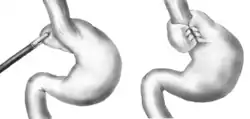

Geste chirurgical

Le traitement chirurgical est la fundoplicature circonférentielle ou partielle. Cette intervention peut se faire par laparoscopie ou laparotomie. Le premier temps opératoire est la correction de la hernie avec repositionnement de la portion herniée de l'estomac dans l'abdomen et redimensionnement de l'orifice hiatal en rapprochant les piliers du diaphragme en arrière de l'œsophage. Le deuxième temps est la création d'une valve antireflux, partielle (type Toupet) ou circonférentielle (type Nissen), ces deux techniques étant d'efficacité équivalente[1].

Des procédures supplémentaires sont parfois effectuées. En cas d'œsophage court, un procédé d'allongement (type Collis) peut être réalisé. Dans certains cas de hernie par roulement, la réparation de l'orifice hiatal est renforcée par une prothèse[1].